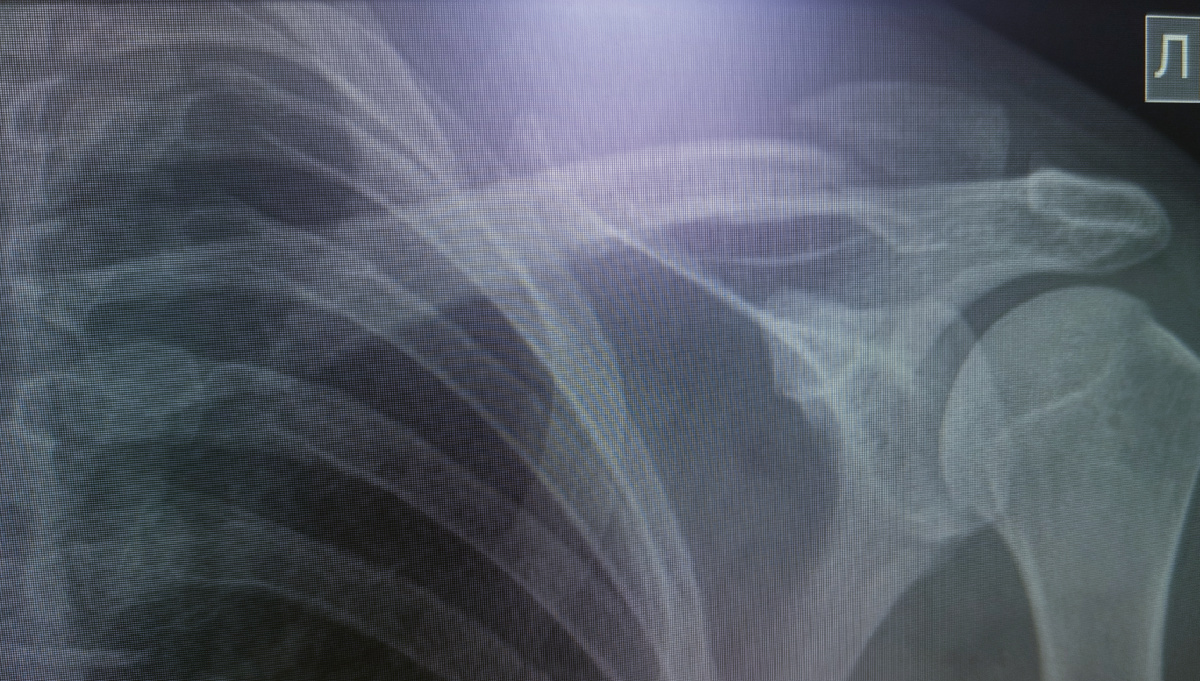

Мужчина пришел , 39 лет . рука заметно висит, назначена ключица.

Сняла , сломана ключица.

–Упал! С велосипеда, прям на руль грудью! Есть там что?

-Есть-есть, идите к травматологам.

Пациенту не стали надевать кольца Дельбе , а сразу предложили поставить пластину. Это я услышала , когда шла по коридору , а пациент делился с кем-то по телефону .